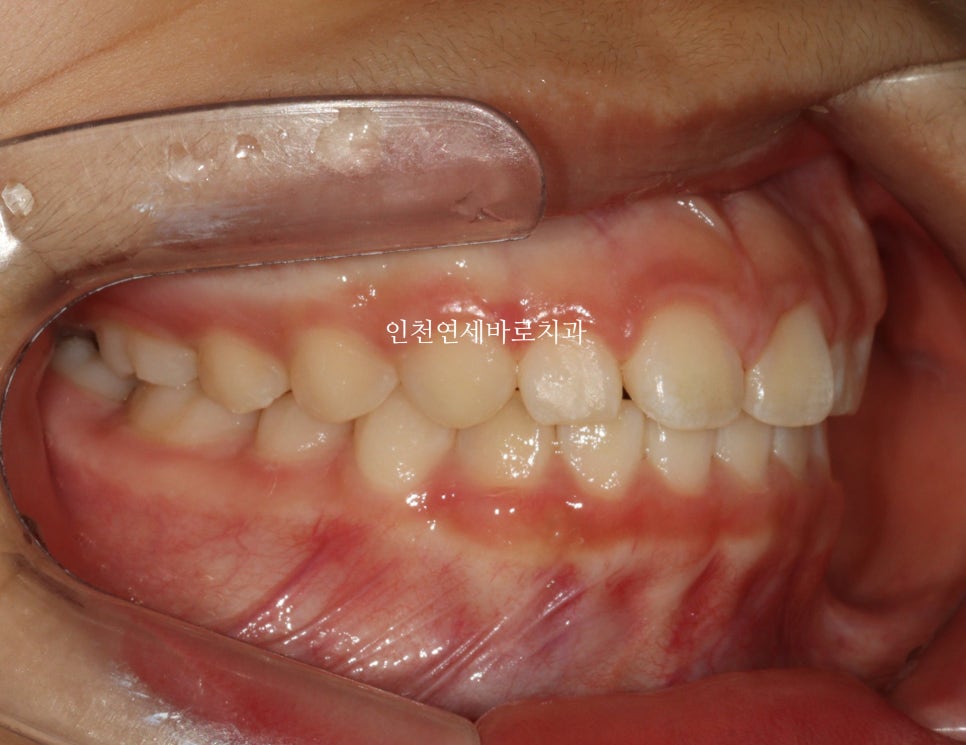

14주 후: 치료 결과

거의완성되었습니다.

거의 라고 말하는 이유는 저희 의료진 눈에는 아주아주 미세한 부분이 마음에 들진 않아서요.

인비절라인 라이트는 1년이라는 기간안에 1회 재제작이 아주 저렴한 비용으로 가능합니다.

이 친구도 정기검진을 하고 25.1.월쯤 아주미세한 부분의 수정을 위해 재제작을 하기로 했어요.

화살표 부분이 약간 아쉬웠기 때문입니다.

저런건 4주정도면 충분하죠.

조금 더 활짝 웃게 된 아이입니다.